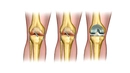

Diz kapağı ameliyatı, diz ekleminde meydana gelen çeşitli rahatsızlıkların tedavisinde uygulanan cerrahi bir müdahaledir. Bu tür ameliyatlar, genellikle diz kapağının yerinden çıkması, yaralanmalar, artrit veya diğer diz problemleri nedeniyle gerçekleştirilir. Ancak, bu tür bir cerrahinin kendi içinde belirli riskler ve sonrasında göz önünde bulundurulması gereken durumlar söz konusudur. Diz Kapağı Ameliyatının RiskleriDiz kapağı ameliyatı, her cerrahi işlemde olduğu gibi bazı riskler taşır. Bu riskler arasında şunlar yer almaktadır:

Uzun Dönem Sonuçlar ve İyileşme SüreciDiz kapağı ameliyatının uzun dönem sonuçları, hastanın genel sağlık durumu, yaş, fiziksel aktivite düzeyi ve rehabilitasyon sürecine bağlı olarak değişkenlik göstermektedir. Genellikle hastalar, ameliyat sonrası birkaç hafta içerisinde günlük aktivitelerine dönebilir. Ancak, tam iyileşme süreci birkaç ay sürebilir. SonuçDiz kapağı ameliyatı, birçok hastada yaşam kalitesini artırma potansiyeline sahip önemli bir cerrahi müdahaledir. Ancak, yaşanabilecek riskler ve ameliyat sonrası bakım süreci göz önünde bulundurulmalıdır. Hastaların, cerrahiden önce ve sonra doktorlarıyla düzenli iletişimde kalarak en iyi sonuçları elde etmeleri hedeflenmelidir. |